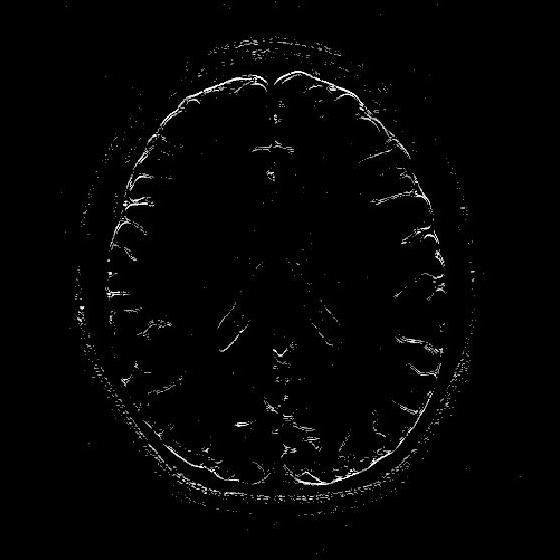

VII-D Application of the 2D-R-FFAST for MR imaging

In this section, we apply the 2D-R-FFAST algorithm to reconstruct a brain image acquired on an MR scanner with dimension . In MR imaging the measurements are acquired in the Fourier domain and the task is to reconstruct the spatial image from significantly less number of Fourier measurements [17]. To reconstruct the full brain image using 2D-R-FFAST, we perform the following two-step procedure:

Differential space signal acquisition: We perform a vertical finite difference operation on the image by multiplying the 2D-DFT signal with . This operation effectively creates an approximately sparse differential image, as shown in Fig. 11(e), in spatial domain and can be reconstructed using 2D-FFAST. Note, that the finite difference operation can be performed on the sub-sampled data and at no point we access all the input Fourier measurements. The differential brain image is then sub-sampled and reconstructed using a stage 2D-FFAST architecture. Also, since the brain image is approximately sparse, we take delay sub-streams in each of the stages of the 2D-FFAST architecture, instead of delay sub-streams as in the exactly sparse case. The 2D-R-FFAST algorithm reconstructs the differential brain image using of Fourier measurements.

-

•

Inversion using fully sampled center frequencies: After reconstructing the differential brain image, as shown in Fig. 11(f), we invert the finite difference operation by dividing the 2D-DFT measurements with . Since the inversion is not stable near the center of the Fourier domain, only the non-center frequencies are inverted. The center region of the 2D-DFT is fully sampled and used in the inversion process.

Overall we use a total of of Fourier measurements to reconstruct the brain image using the 2D-R-FFAST algorithm along with the fully sampled center frequencies. The resulting signal-to-noise ratio of the reconstructed image is dB. While the reconstruction error is not as good as state-of-the-art compressed sensing MRI results, we note that the 2D-R-FFAST has both low computational complexity and low sample complexity , which none of the state-of-the-art compressed sensing results in MRI can achieve.